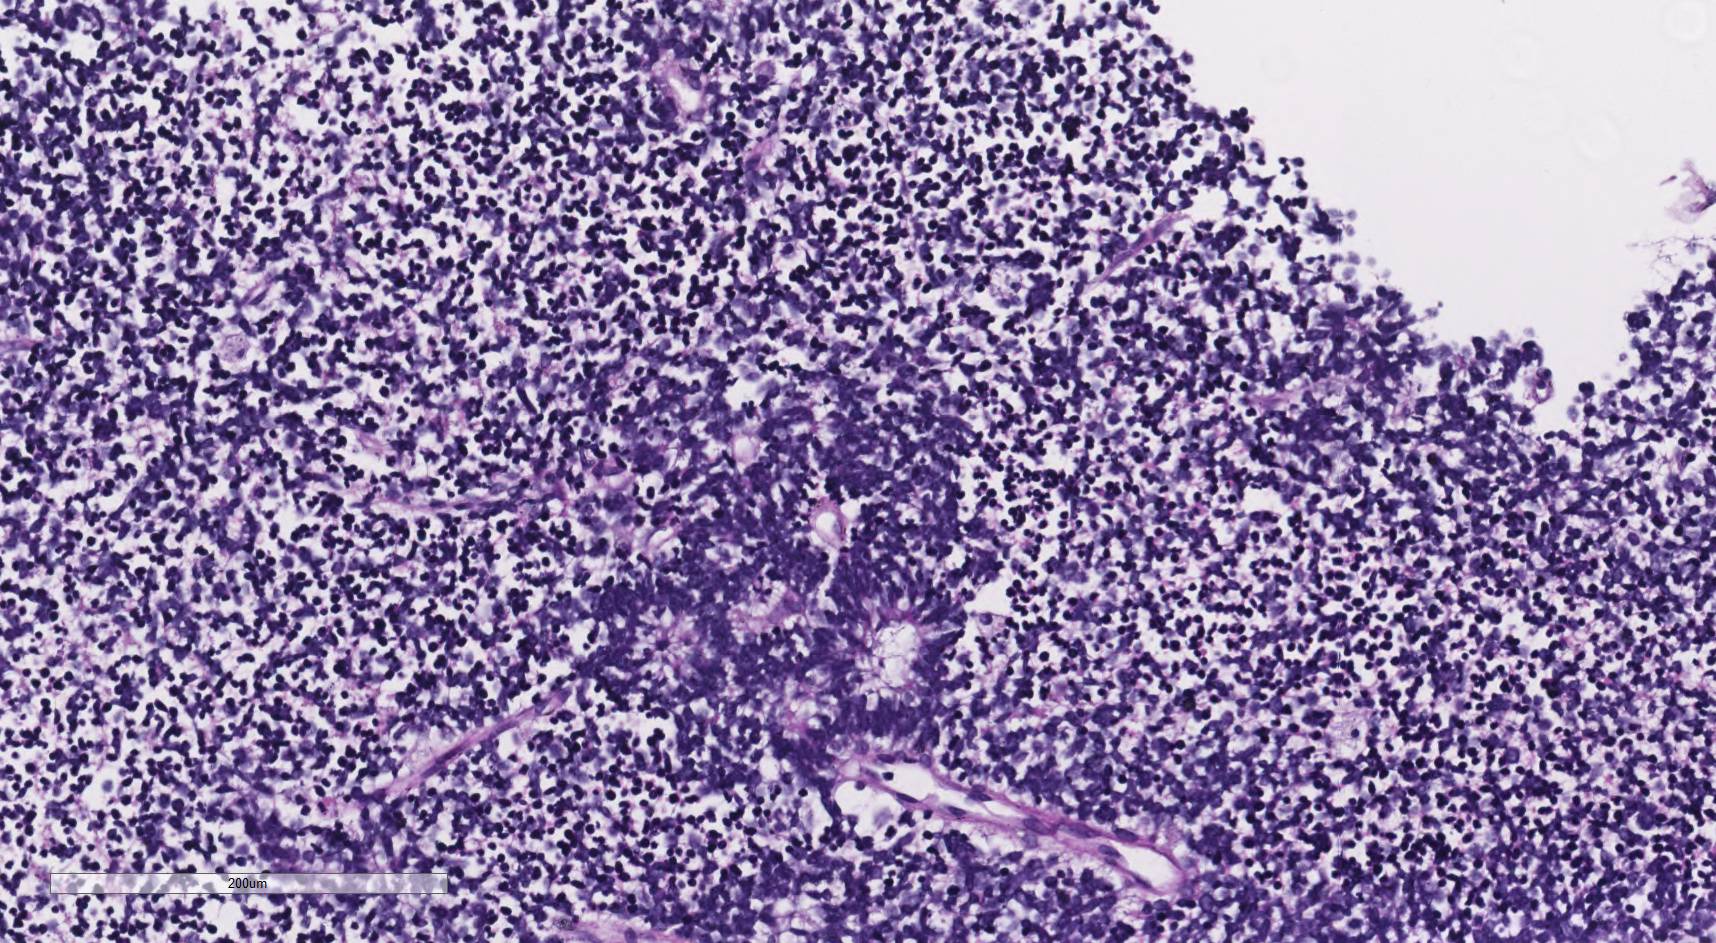

Diagnostico: Tumor embrionario con rosetas de múltiples capas.

Discusión: Entidad incorporada en la clasificación de la OMS 2016, dentro de los tumores embrionarios, que puede mostrar tres patrones morfológicos: tumor embrionario con abundante neuropilo y verdaderas rosetas, ependimoblastoma y meduloepitelioma. Expresa en forma variable sinaptofisina, vimentina y CD99, y LIN28A independientemente del patrón morfológico. Típicamente presenta alteración C19MC (90%) que incluyen amplificaciones o fusiones, y raramente mutación DICER1 (5%). Se presenta por lo general en niños menores de 4 años, como voluminosas masas intracraneales tanto en el compartimiento supra e infratentorial, son de rápido crecimiento y están asociados con un curso clínico agresivo.